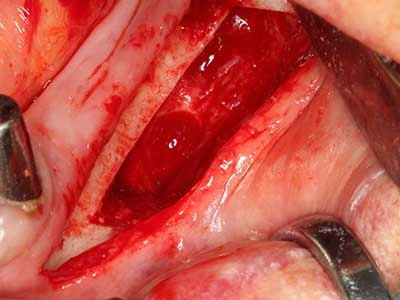

When surgical procedures are performed on bone in the immediate vicinity of sensitive structures such as blood vessels or nerves, rotary instruments pose a significant risk of iatrogenic injury. Piezoelectric devices can be helpful for preparation of bone covers and removal of hard tissue close to nerves, particularly for exposure of nerves after iatrogenic injury but also during nerve lateralization for resective and reconstructive procedures or implant placement (Fig. 17-20). Light contact between the piezotip and the nerve does not generally result in damage but proceeding incautiously with saw-like motions or attachments where a residual bone substrate remains may cause temporary or even permanent nerve damage. However, the risk of damage is considered to be substantially lower than when using saws or milling instruments (Pereira, Gealh et al. 2014).